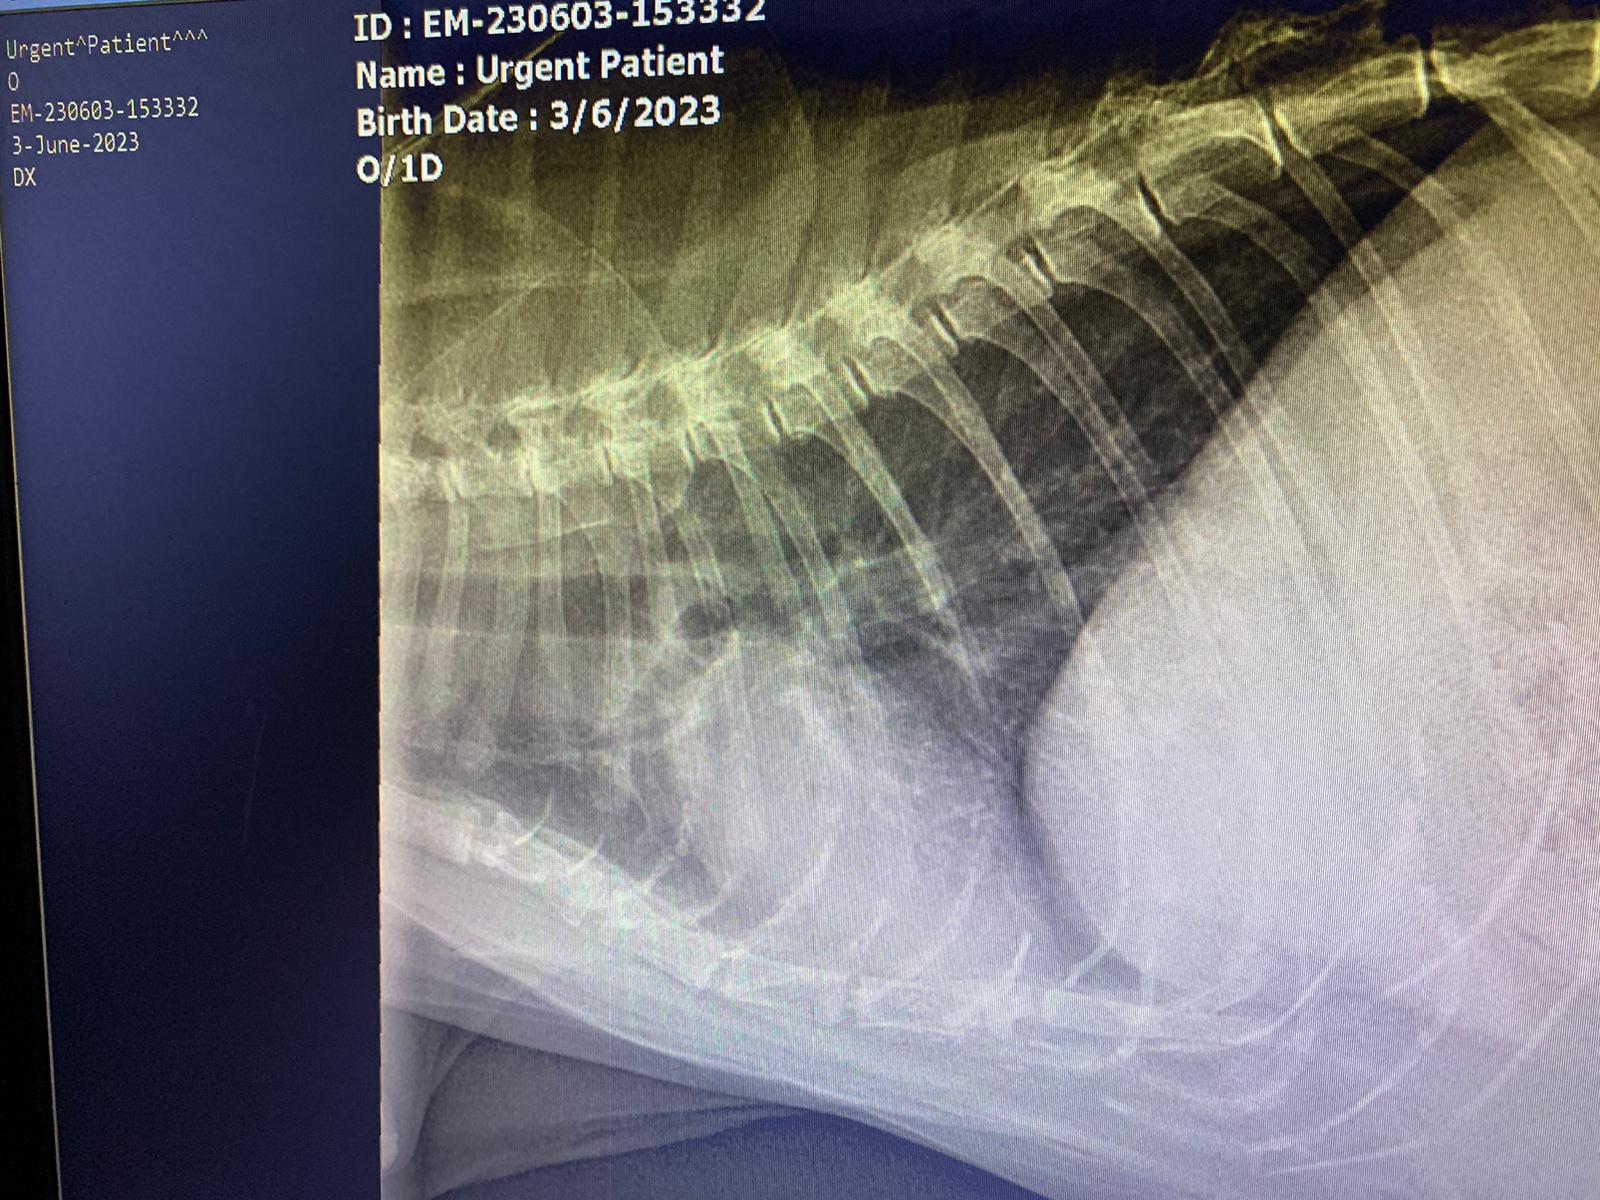

Dr nally says don’t like the muffed sound of his lung, noisy, i scare got fluid ah. Taken X-ray.

X-ray show he got one lump of fluid on the left, cannot confirm what it is. Unless abdominal u/s – I rather spend money on bupre.

His lower spine one part should be in pain.